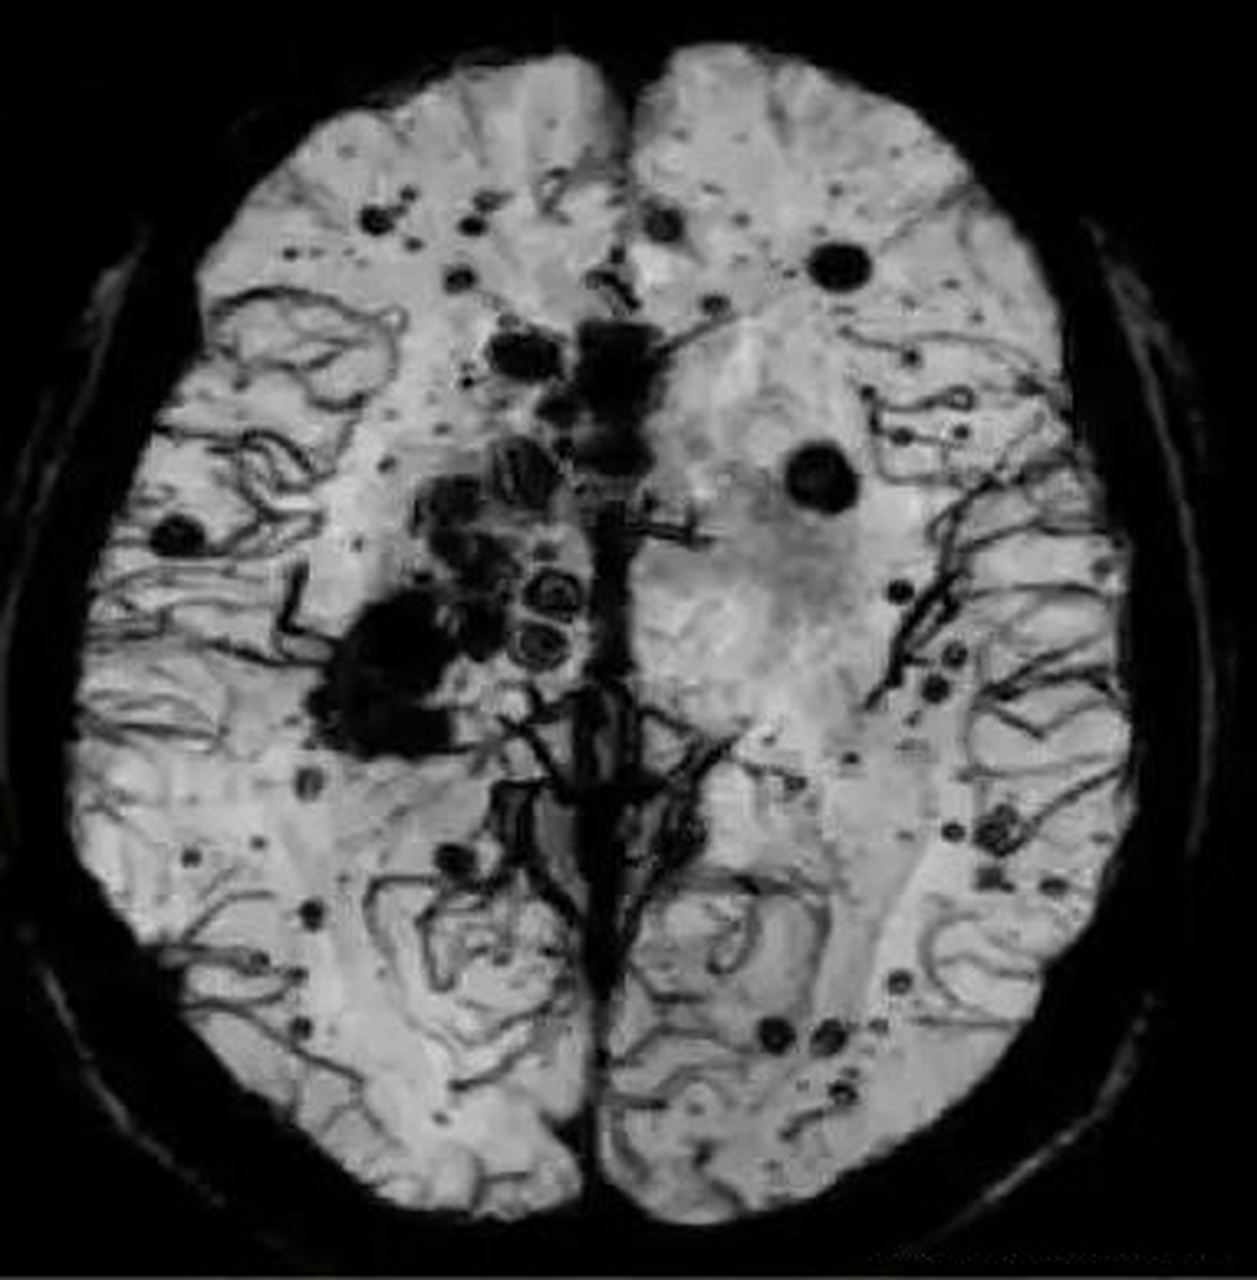

淀粉样变性脑血管病的影像诊断